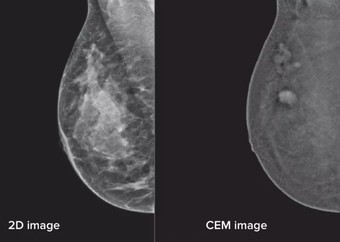

CEM is part of your breast assessment. It gives us more detailed information than just using standard mammography as seen below. The image shows the lesions in the breast brighter on the CEM image than a standard 2D mammogram.

Mammography scan images, on the left 2D imaging, on the right contrast enhanced imaging